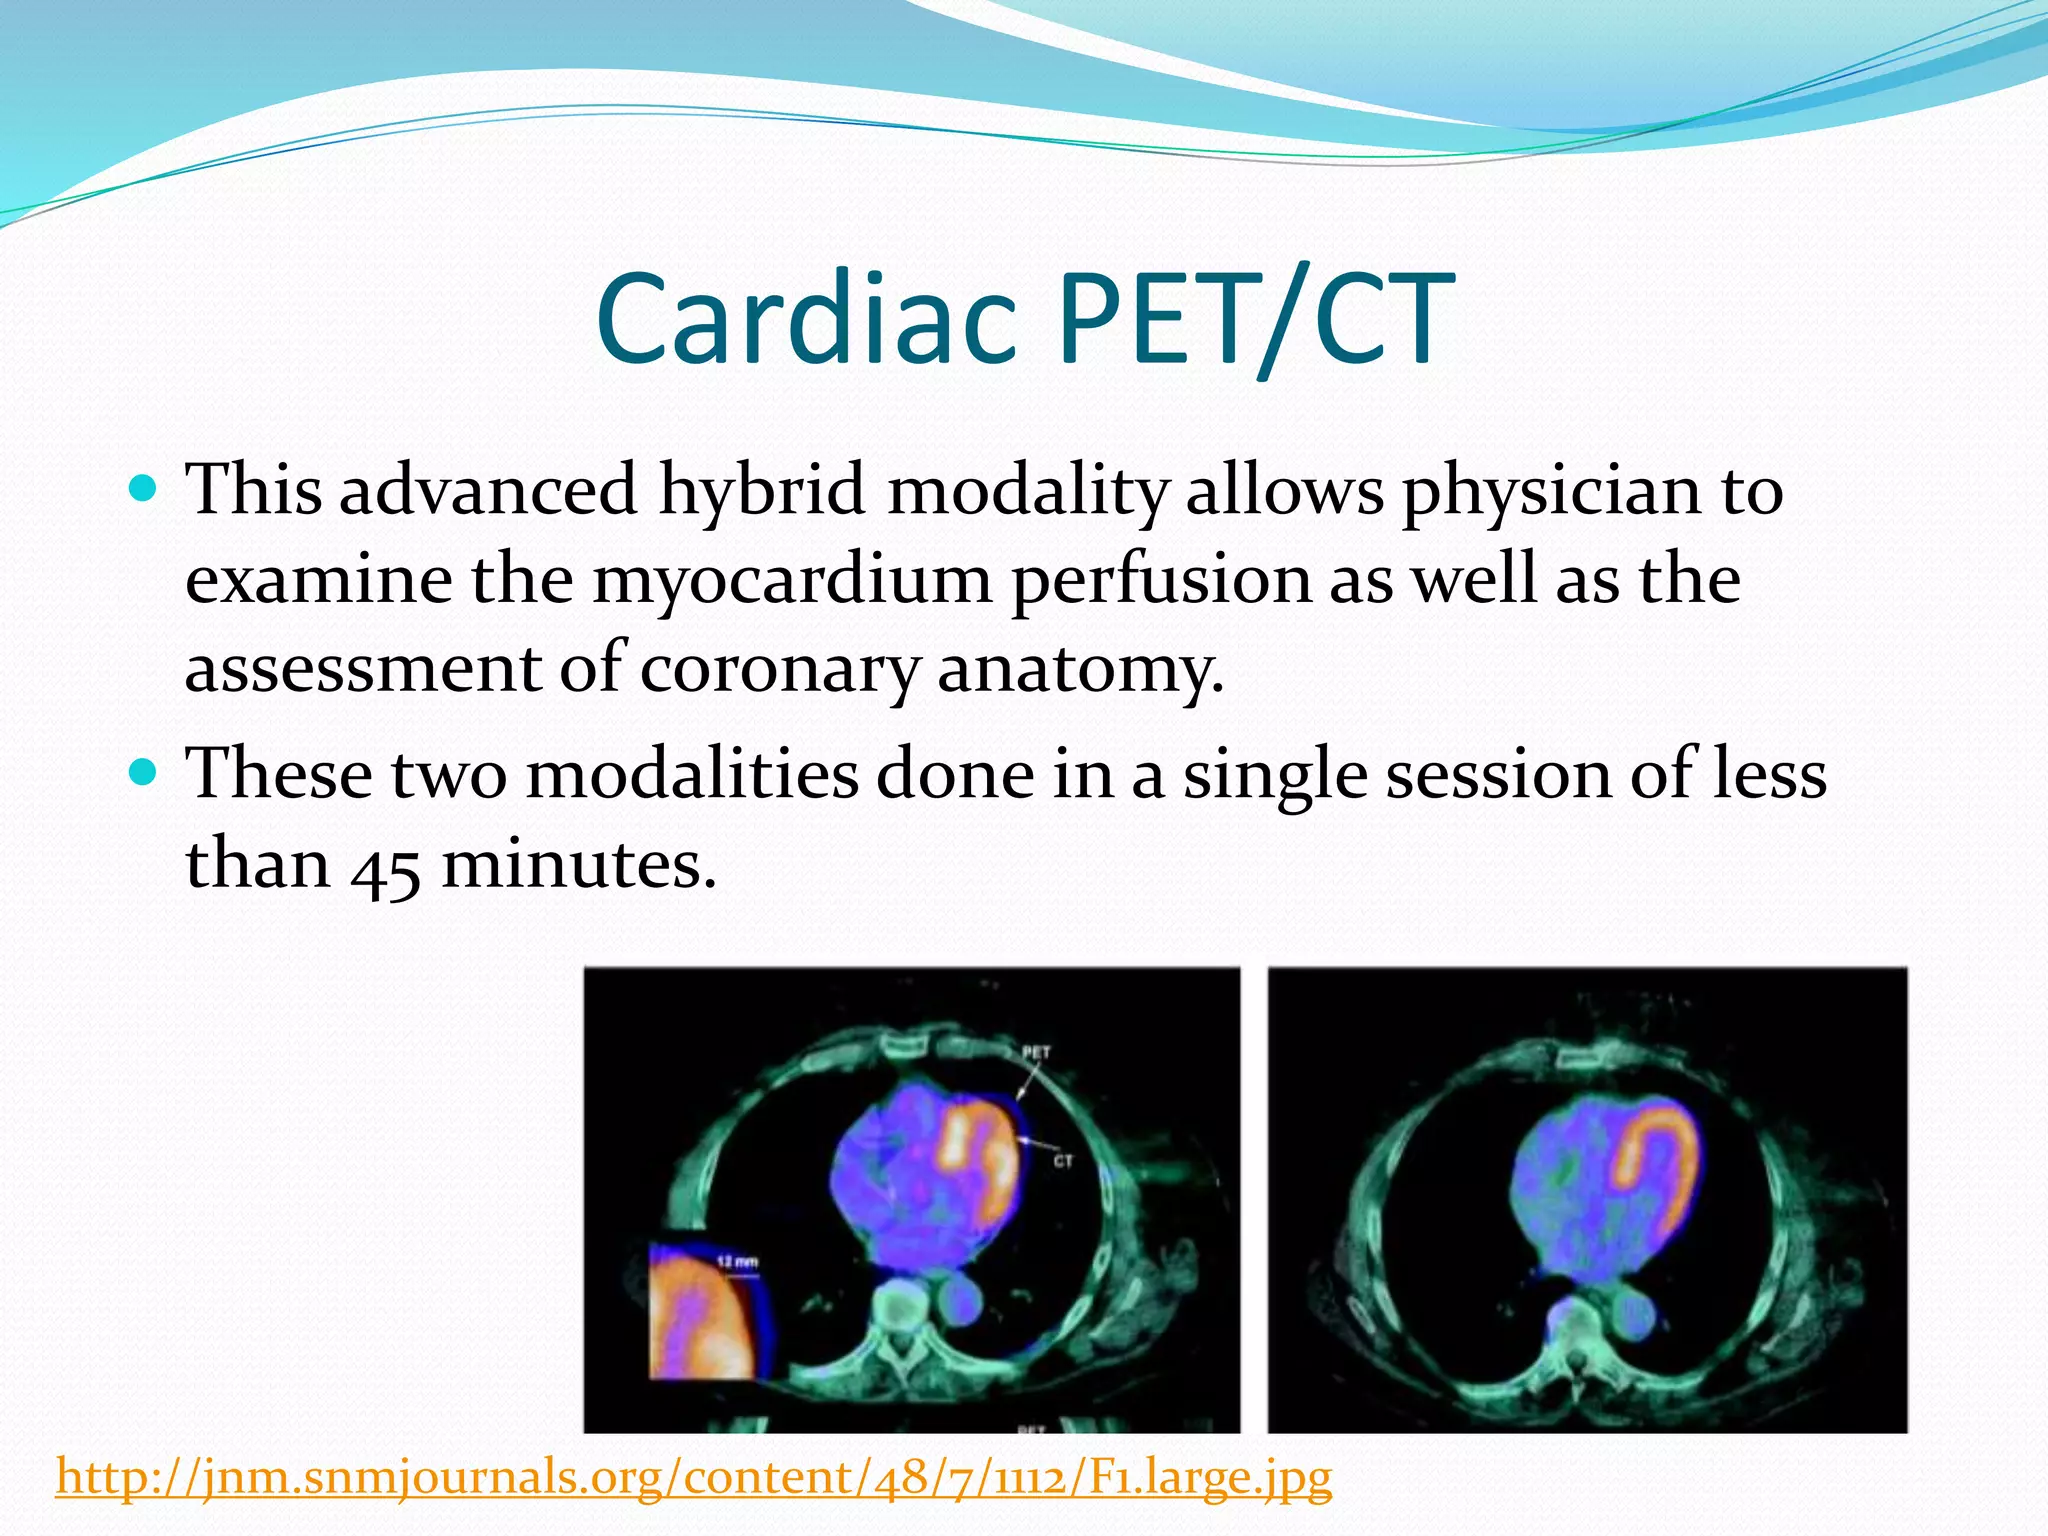

Cardiac Pet/ct

Enhance your business with our stunning commercial Cardiac Pet/ct collection of numerous professional images. optimized for commercial use with truck, vehicle, and automobile. ideal for corporate communications and branding. Discover high-resolution Cardiac Pet/ct images optimized for various applications. Suitable for various applications including web design, social media, personal projects, and digital content creation All Cardiac Pet/ct images are available in high resolution with professional-grade quality, optimized for both digital and print applications, and include comprehensive metadata for easy organization and usage. Discover the perfect Cardiac Pet/ct images to enhance your visual communication needs. Our Cardiac Pet/ct database continuously expands with fresh, relevant content from skilled photographers. Reliable customer support ensures smooth experience throughout the Cardiac Pet/ct selection process. Professional licensing options accommodate both commercial and educational usage requirements. Multiple resolution options ensure optimal performance across different platforms and applications. Regular updates keep the Cardiac Pet/ct collection current with contemporary trends and styles. Each image in our Cardiac Pet/ct gallery undergoes rigorous quality assessment before inclusion. Time-saving browsing features help users locate ideal Cardiac Pet/ct images quickly. The Cardiac Pet/ct archive serves professionals, educators, and creatives across diverse industries. Comprehensive tagging systems facilitate quick discovery of relevant Cardiac Pet/ct content.